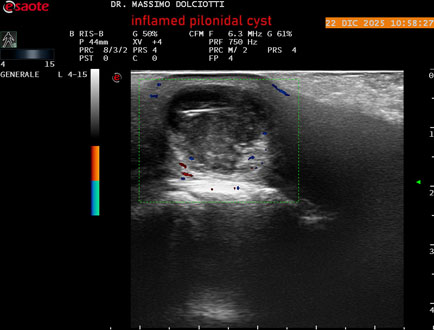

Ecografia del: 22/12/2025

Strumento: Esaote MyLab Eight

Sonda: Lineare Multifrequenza 4-15 MHz

Età Paziente: M 29 anni

Motivazione dell'esame: da 3.giorni dolore, tumefazione ed arrossamento in regione coccigea

Commento all'esame: le immagini ed il video documentano formazione anecogena in sede coccige, delle dimensioni di 24,6 x 18,8 mm, da ricondurre a cisti pilonidale flogosata.

Conclusioni: cisti pilonidale flogosata (inflamed pilonidal cyst).